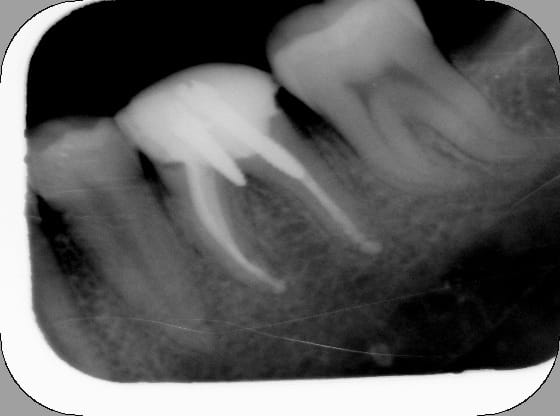

c'est pas de moi et ça fait 20 ans que ça tient :-)))

Gui bliwfj - Eugenol

24/02/2009 à 18h53

ce n'est pas de moi!!!

11 mvu8po - Eugenol

Kon nx3ojp - Eugenol

wow

si la cortical externe de la mandibule avait été moin dur il serai ressorti par la peau... :)

impressionant la rx que tu nous as postée.

Quels symptomes présentaient le patient? comment l'as tu géré?

la patiente ne présentait aucun symptôme lié aussi bien au dépassement de l'instrument qu'à la pâte

extraction par un collègue spécialisé en Chirurgie buccale

tout est venu d'un seul tenant